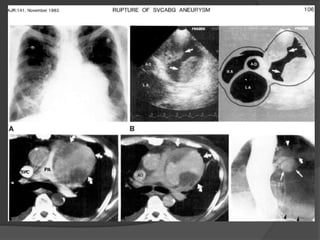

Case A 3:

73 year old male , R/O mass,

heart attack

Dx: Ruptured coronary graft pseudoaneurysm with

hemothorax

•Late complication of coronary bypass surgery

•Most aneurysms associated with saphenous

vein CABGs occur at the anastomotic sites.

Sutural defects, structural weakness of the

parent artery, deficiency in the preparation of

the saphenous vein and progressive

atherosclerosis

•Mediastinal or hilar mass on radiographs,

vascular nature of the mass on CECT or MRI,

extent and mass effect

•Complications of graft aneurysmal disease

are thrombosis, thromboembolism, fistula

formation to the right atrium or ventricle,

rupture and MI